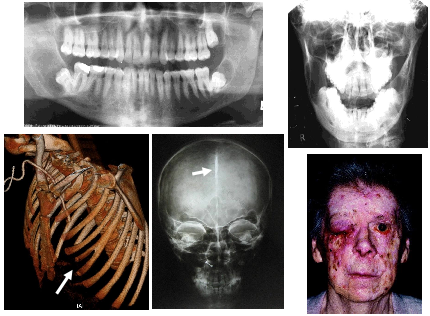

What is an Odontogenic myxoma?

Origin: Odontogenic connective tissue fibroblasts of the developing tooth germ.

Age: Young adults 2nd-4th decades

Frequency: Rare

Site: Posterior maxilla or mandible

Size: Variable

Shape: Multilocular – honeycomb or soap bubble

Outline: Well defined with variable cortication

Radiodensity: Radiolucent with fine radiopaque internal septa often arranged at right angles to each other

Effects: Displaced teeth occasionally resorbed, may be associated with an un erupted tooth cortical expansion / breach.